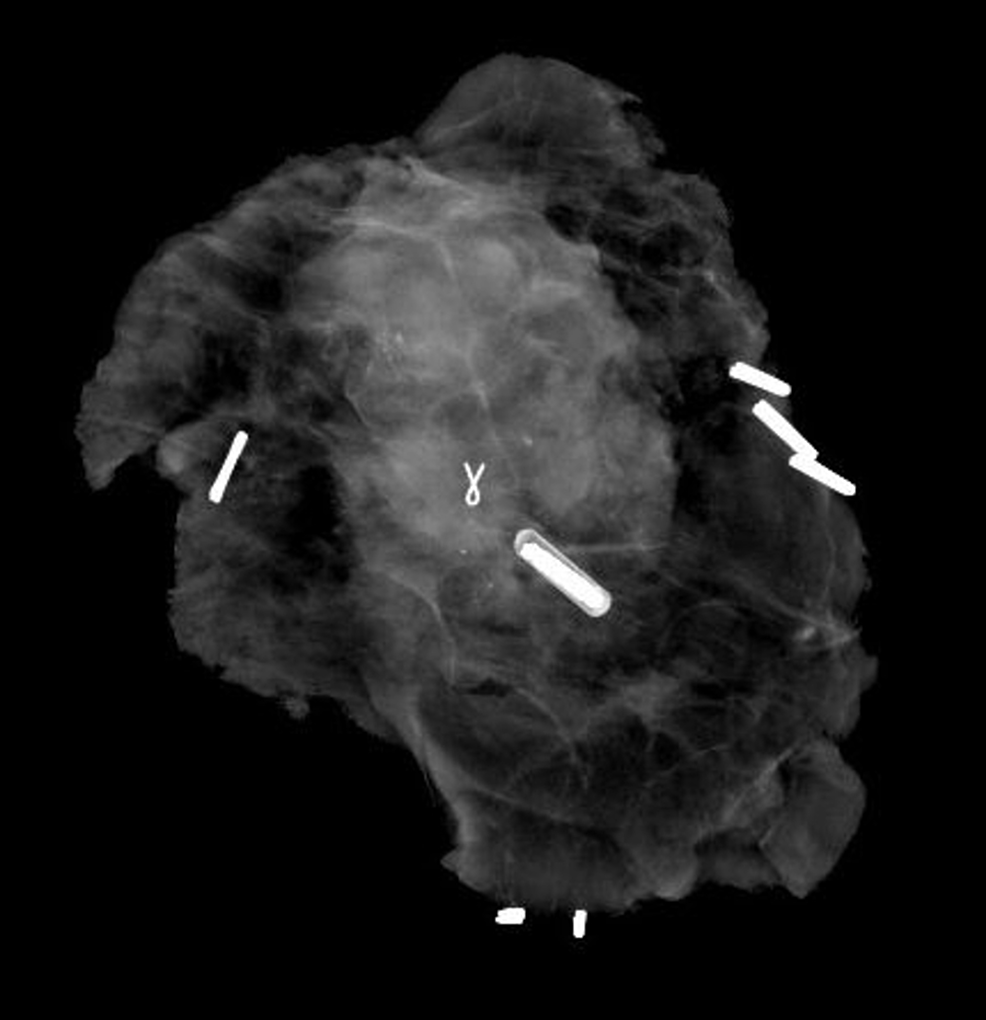

MRI Breast Biopsy Section B Basic Biopsy Technique for Radiologists

Breast Resonance Imaging for the Interventionalist Titanium Implants Breast Biopsy Web if you’ve had a surgical biopsy on your breast (or you’re about to get one), you may know that your doctor uses a tiny. In the last decade, percutaneous breast biopsies have become a standard for the management of breast diseases. Web allergic reactions to titanium, a component of both hydromark, mammomark, and cormark biopsy. Titanium Implants Breast Biopsy.

Resonance Imaging of Breast Cancer and Resonance Titanium Implants Breast Biopsy In the last decade, percutaneous breast biopsies have become a standard for the management of breast diseases. Web allergic reactions to titanium, a component of both hydromark, mammomark, and cormark biopsy. Web if you’ve had a surgical biopsy on your breast (or you’re about to get one), you may know that your doctor uses a tiny. Titanium Implants Breast Biopsy.

Troubleshooting to Technical Challenges in Imageguided Breast Titanium Implants Breast Biopsy Web if you’ve had a surgical biopsy on your breast (or you’re about to get one), you may know that your doctor uses a tiny. Web allergic reactions to titanium, a component of both hydromark, mammomark, and cormark biopsy. In the last decade, percutaneous breast biopsies have become a standard for the management of breast diseases. Titanium Implants Breast Biopsy.

Pathology Outlines Breast biopsy marking devices Titanium Implants Breast Biopsy Web if you’ve had a surgical biopsy on your breast (or you’re about to get one), you may know that your doctor uses a tiny. Web allergic reactions to titanium, a component of both hydromark, mammomark, and cormark biopsy. In the last decade, percutaneous breast biopsies have become a standard for the management of breast diseases. Titanium Implants Breast Biopsy.